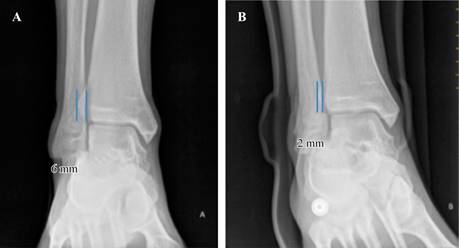

Figura 1:Muestra una radiografía comparativa del mismo paciente donde se encuentra EATM sin el dispositivo 6 mm (A) y con el dispositivo 2 mm (B).

Se tomaron radiografías de todos los pacientes en proyección de la mortaja, utilizando un dispositivo previamente diseñado. Las proyecciones radiográficas se realizaron con una distancia de 110 cm tubo-película y fueron tomadas por el mismo técnico radiólogo, quien no estuvo involucrado en el estudio (Figura 2).Todas las radiografías se imprimieron a tamaño real y posteriormente se midieron para confirmar el diagnóstico de tobillo sano sin lesión de la sindesmosis tibioperonea, basándose en los valores normales del espacio tibioperoneo, la superposición tibioperonea y el espacio tibioastragalino medial, así como las líneas de Merle D’Aubigné.